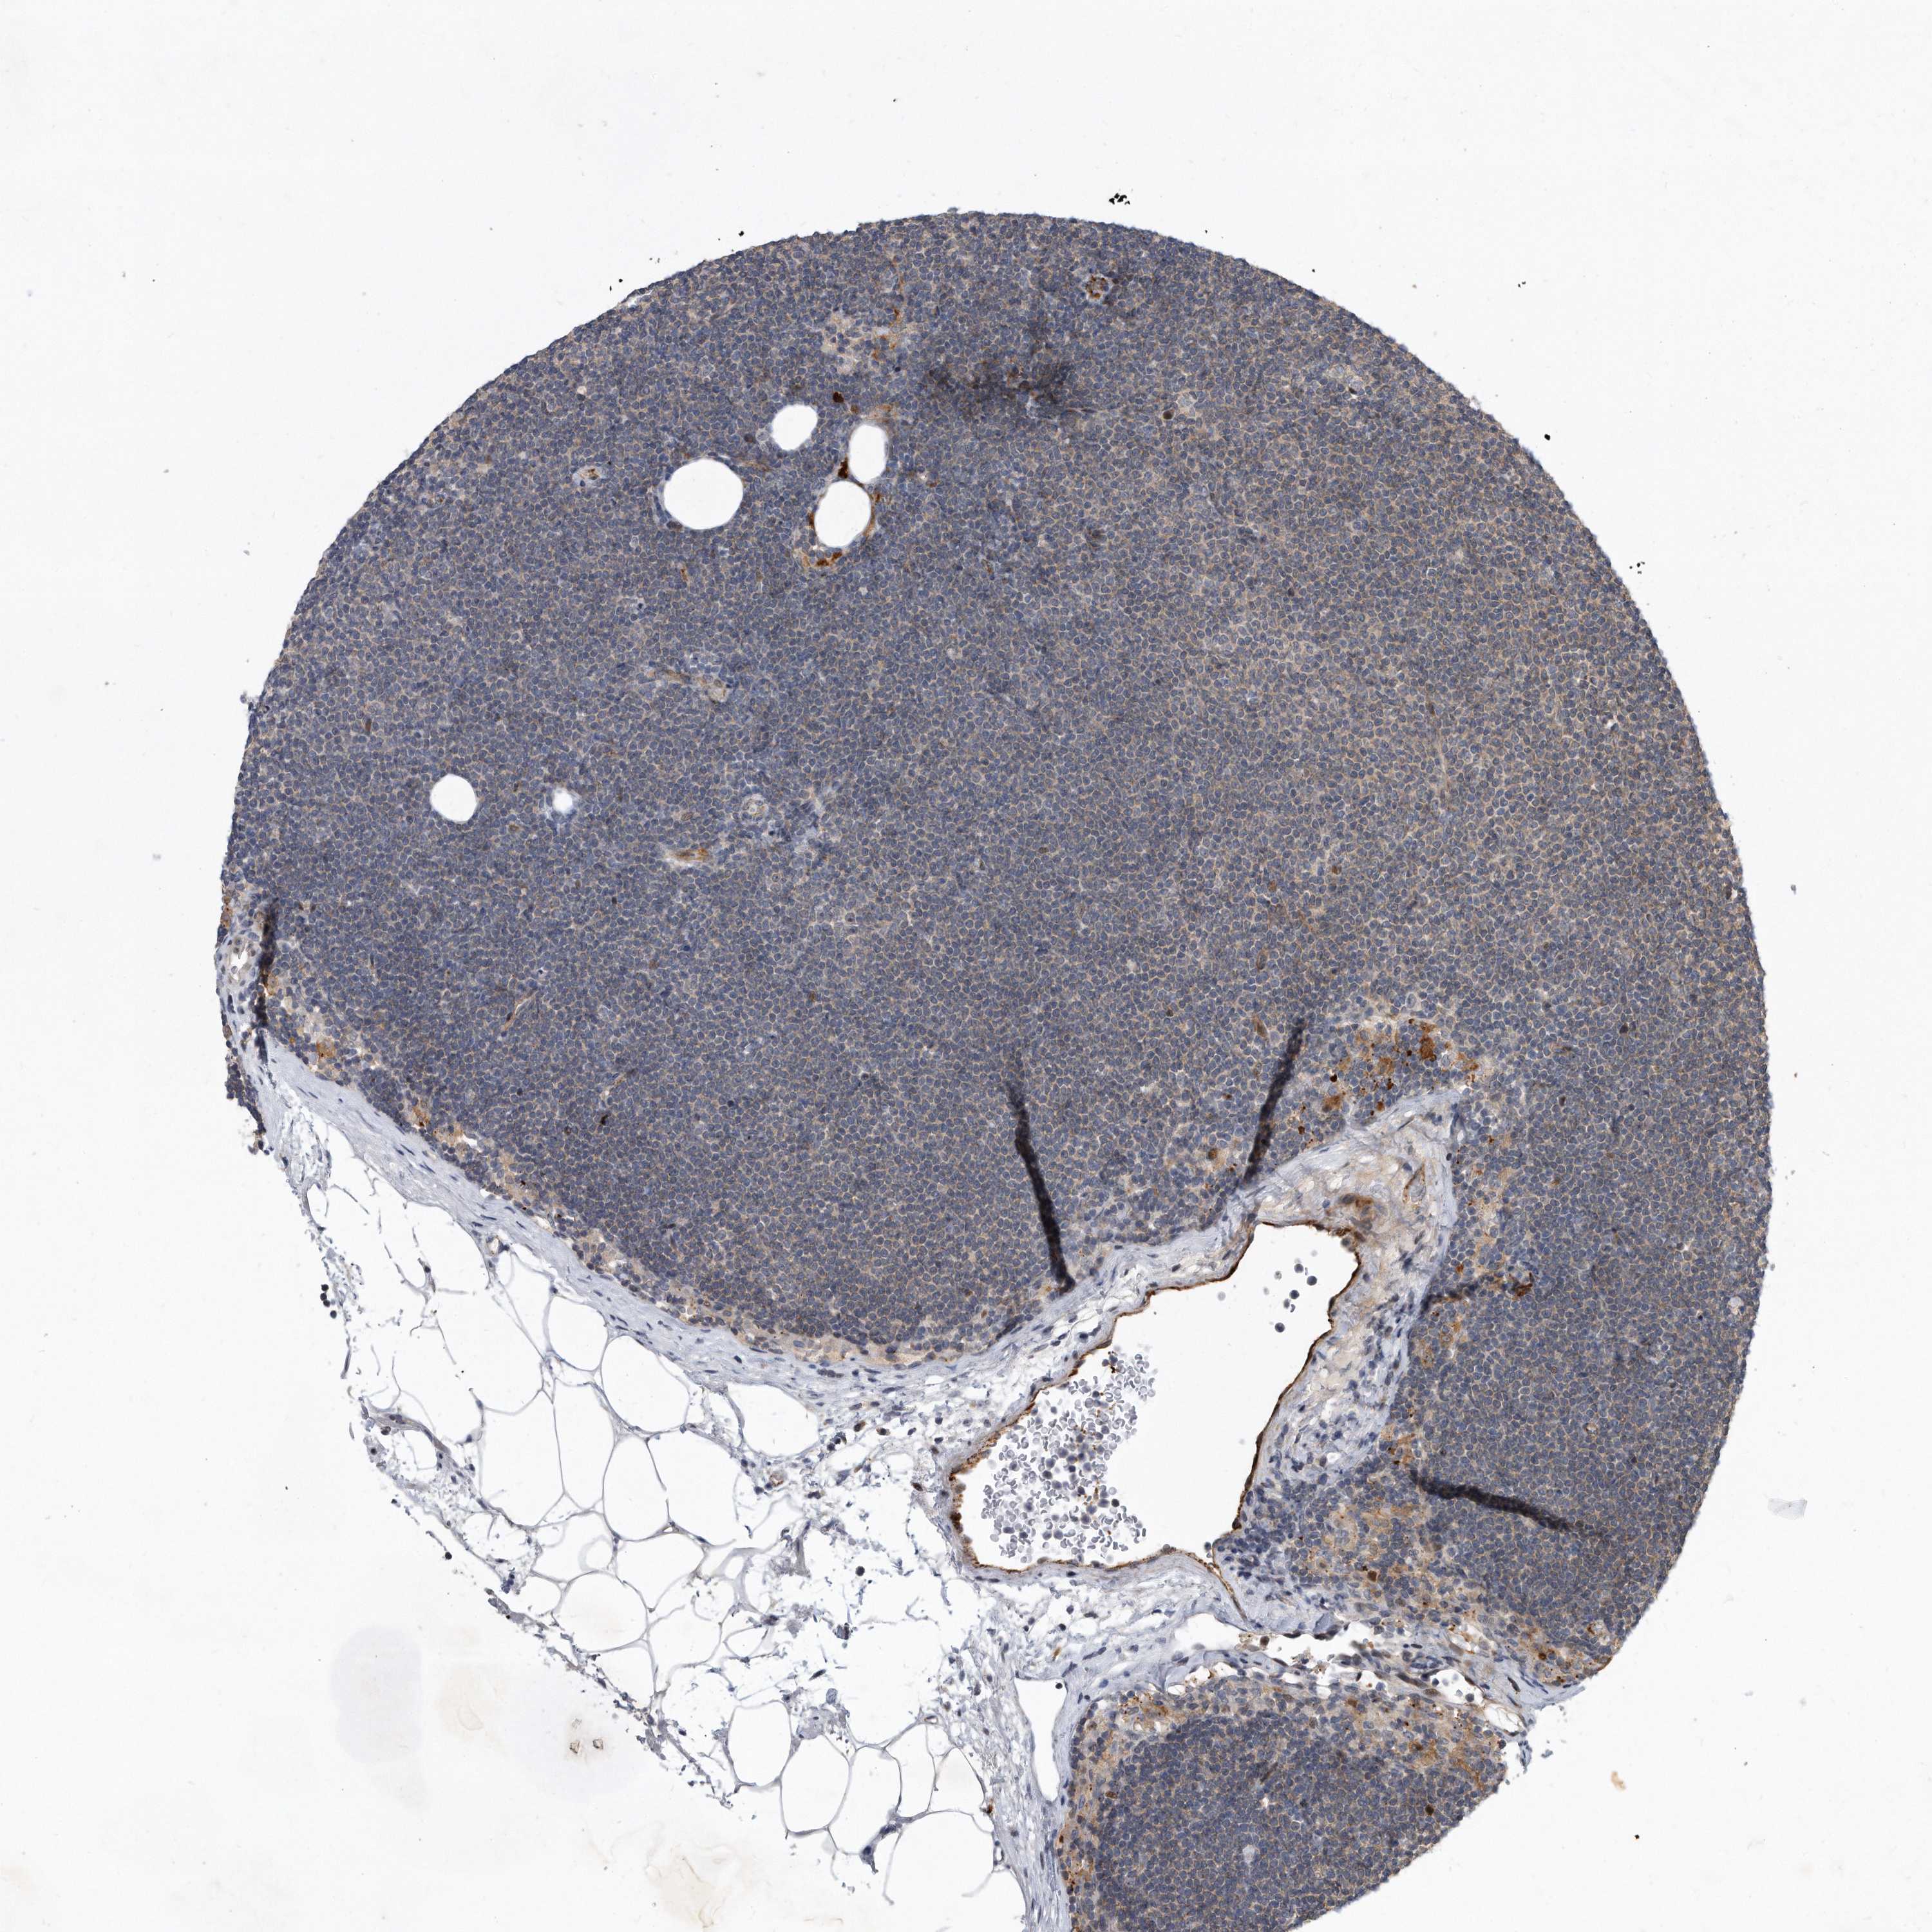

CANCER LYMPHOMA Show tissue menu

LYMPHOMA - Protein expressioni

A mouse-over function shows sample information and annotation data. Click on an image to view it in a full screen mode. Samples can be filtered based on level of antibody staining by selecting one or several of the following categories: high, medium, low and not detected. The assay and annotation is described here.

Each image is clickable and will lead to virtual microscopy that enables deeper exploration of all samples and also displays staining intensity scores, fraction scores and subcellular localization as well as patient and tissue information for each sample.

Antibody HPA029888

Antibody HPA029889

Antibody HPA029890

Hodgkin's disease, NOS

Malignant lymphoma, non-Hodgkin's type, High grade

Malignant lymphoma, non-Hodgkin's type, Low grade